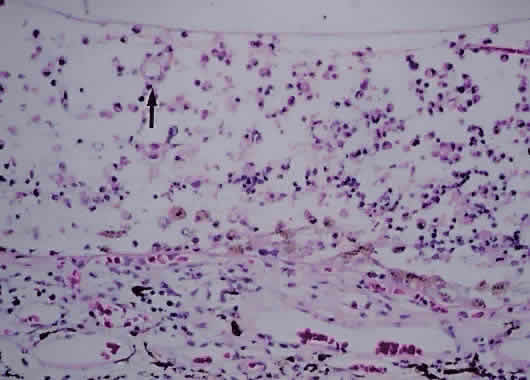

Early events in EAU include expression of adhesion molecules on the surface of retinal vascular endothelium, allowing the adherence of circulating leukocytes and subsequent infiltration into the retina.22,23 In Lewis rats, the acute cellular infiltrate is composed of neutrophils and primarily affects the retina (Fig. 3) and anterior segment.24 CD4+ T cells have been found necessary for the development of EAU25 and are stimulated by presentation of antigen in the setting of MHC class II-expressing cells.26 There is likely a genetic susceptibility to the development of EAU,27 which may help explain occurrence of uveitis in only certain individuals. Once initiated, much of the damage resulting from EAU, and most likely in human uveitis, is caused by the production of numerous oxygen-derived radicals (e.g., superoxide, hydrogen peroxide, hydroxyl radicals, peroxynitrite), which directly attack the photoreceptor layer, producing oxidative damage to these sensitive light-sensing cells.28–30

Fig. 3. Photomicrograph of retina of Lewis rat 13 days after injection of S antigen in complete Freund's adjuvant to hind footpad. Inflammatory cell infiltrate exists within the retina as well as in the subretinal space. Photoreceptor layer is destroyed (hematoxylin and eosin; × 200).